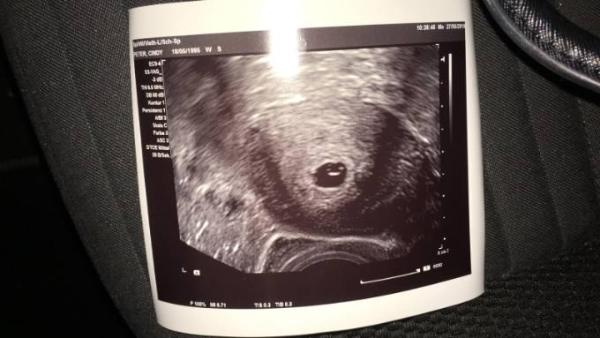

Hey ihr lieben :) hatte heute meinen 1. FA-Termin 5+5 SSW (war eigl. für morgen angedacht, hatte aber seit gestern Mittag NIerenschmerzen links). Ultraschall war super, Dottersack hat man gesehen, das Krümelchen leider noch nicht, aber der Frauenarzt war so einfühlsam, habe ihm erzählt, dass wir Freitag Nacht in Urlaub fliegen für 2 Wochen: er meinte dann es sei kein Problem, wenn ich mir sorgen mache wegen dem Krümel kann ich gerne nochmal am Freitag kommen und wir schauen ob das Herzchen schlägt, Blut hat er mir auch gleich abgenommen (obwohl sie das erst in 2 Wochen gemacht hätten). Drückt mir die Daumen, dass das Herzchen am Freitag schon schlägt und ich voller Freude in unseren Urlaub starten kann :) PS: Findet ihr auch, dass es lächelt? :D

Bild zu erster FA-Termin geschafft  - Forum für Januar - Mamis

Was ist denn dann das weiße im dottersack? Freitag sieht man sicher mehr.

weis ich nicht, vielleicht mein Würmchen? :D Ja bestimmt :))